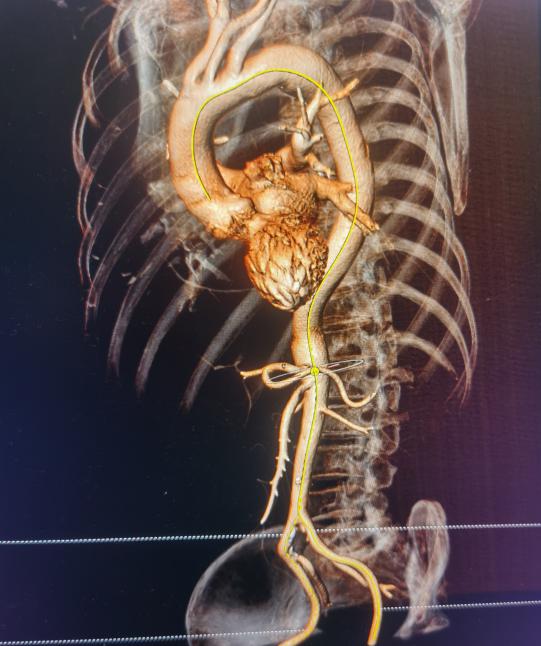

姜永红主任团队对老人病情进行细致分析,因患者高龄,既往有多种慢性病史,无法耐受开胸主动脉瓣置换术,患者主动脉狭窄伴关闭不全,以关闭不全为主,对手术提出了更高的要求。科室及时把老人病情上报医院医务科,院领导高度重视,并多次组织心血管内科、介入科、超声医学科、重症医学科、麻醉手术科、体外循环医师及辅助科室共同讨论,制定手术方案,建议行TAVR手术。于8月3日在心外科医护人员共同努力下,行经股动脉经导管主动脉瓣置换术,手术过程顺利,效果满意。患者术后次日下床活动,精神状态良好。

经导管主动脉瓣置换术(TAVR)是指将组装好的主动脉瓣经导管置入到主动脉根部,替换原有的主动脉瓣,在功能上完成主动脉瓣的置换。TAVR手术是近年来国际上开展的一种新的手术方式,近年来在国内大心脏中心陆续开展,在地市级医院还属于起步阶段。跟外科的开胸手术来对比,TAVR创伤非常小,不需要锯开胸骨及建立体外循环、心脏停跳等危险因素,大大降低了手术风险和术后并发症的发生。对于一些老年人及心功能较差不能耐受开刀手术的心脏瓣膜病人,是一种很好的治疗方式。